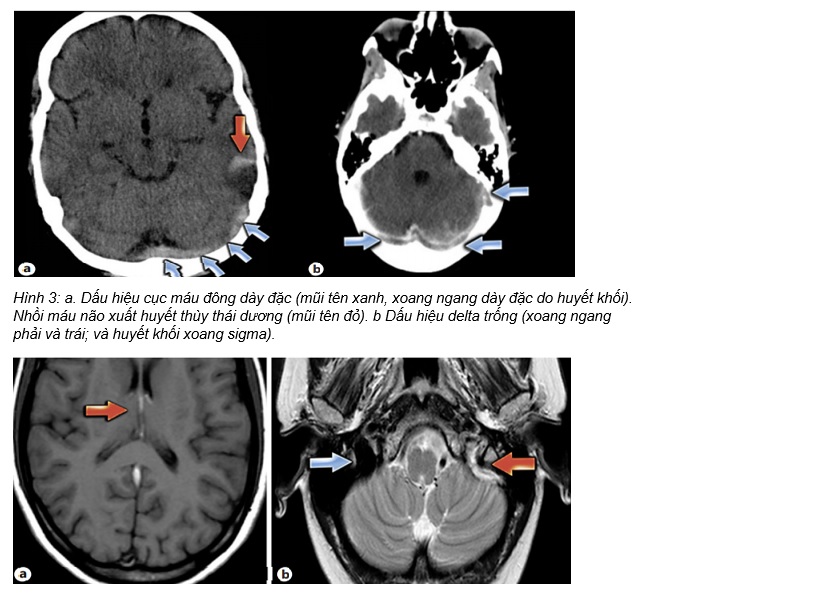

BN chụp CT không cản quang

CT: nhồi máu não chuyển dạng xuất huyết vùng thái dương phải

MRI: huyết khối xoang ngang; MRV : Tắc nghẽn xoang ngang phải

Huyết khối xoang ngang phải /Nhồi máu não chuyển dạng xuất huyết thùy thái dương phải.

CT đầu nên được thực hiện trong cấp cứu để loại trừ xuất huyết và thoát vị não. Tìm:

• Dấu hiệu delta trống (Empty delta sign) – dòng chảy trống trong xoang dọc sau do huyết khối xoang dọc trên.

• Dấu hiệu xoắn ốc (Corkscrew sign) – các nhánh tĩnh mạch giống hình dạng “xoắn ốc” sau khi hình thành huyết khối tĩnh mạch. MRI với MRV nên được chỉ định để hình dung mức độ tổn thương nhu mô não và hệ thống dòng chảy tĩnh mạch. Nó nhạy hơn CT scan nhưng không phải là 100%. Chụp mạch máu xóa nền (Digital subtraction angiography, DSA) là tiêu chuẩn vàng trong việc chẩn đoán nhưng không phải trung tâm nào cũng có.

Chụp cắt lớp vi tính

Hình ảnh chẩn đoán ban đầu được khuyến cáo là chụp cắt lớp vi tính (CT) không cản quang cho tất cả bệnh nhân có biểu hiện của các triệu chứng thần kinh cấp tính như nhức đầu, thiếu hụt thần kinh khu trú, thay đổi trạng thái tâm thần và co giật. Trong khoảng 30% trường hợp, CT có thể bình thường hoặc cho thấy những bất thường không đặc hiệu; do đó, chụp cắt lớp thông thường không loại trừ được CSVT. CT không cản quang cho thấy các dấu hiệu trực tiếp như dấu hiệu cục máu đông dày đặc (dense clot sign ) (cục máu đông trong tĩnh mạch não và xoang) và dấu hiệu chuỗi hoặc dây (string or cord sign ) (string or cord-like density indicating CSVT); cũng như các dấu hiệu gián tiếp như phù não, hiệu ứng khối, và xuất huyết nội sọ có thể từ các tổn thương nhỏ cận vỏ (juxtacortical ) đến xuất huyết dưới nhện và các ổ xuất huyết lớn. CT tăng cường chất cản quang cho thấy các dấu hiệu trực tiếp như dấu hiệu delta trống(empty delta sign ) (a low-attenuated center surrounded by a triangular area of contrast enhancement) và các dấu hiệu gián tiếp, tương tự như CT không cản quang